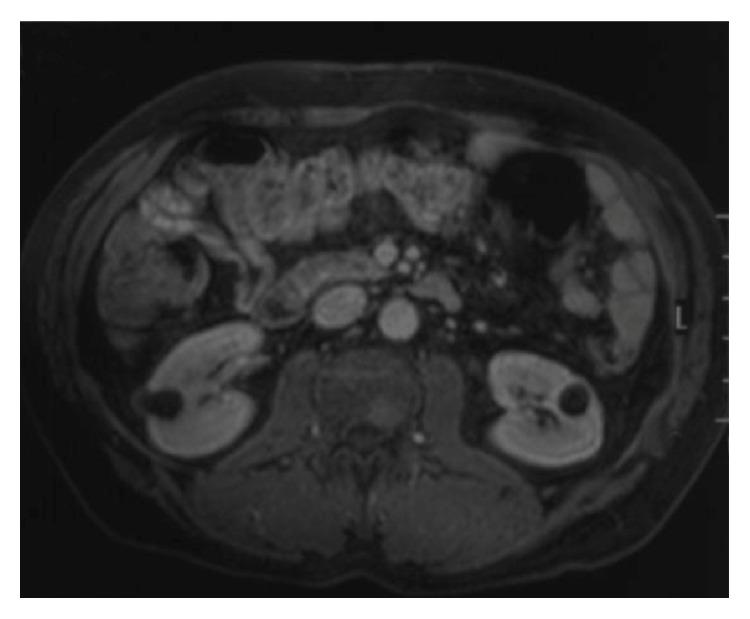

We describe an unusual case of hairy cell leukemia (HCL) in a 55-year-old male presenting with isolated skeletal disease as the initial manifestation without abnormal peripheral blood counts, bone marrow involvement, or splenomegaly. To the best of our knowledge, there have been only two previous reports of a similar case. The patient presented with pain in the right femur. Anteroposterior radiographs of both femurs revealed mixed lytic-sclerotic lesions. PET scan showed multiple metastatic lesions on axial skeleton, pelvis, and both femurs. Histopathological examination of the bone biopsy revealed an infiltrate of HCL. Localized radiation therapy to both proximal femurs and subsequently 4 weeks later, a 7-day course of 0.1 mg/kg/day cladribine provided complete remission with relief of symptoms and resolution of bone lesions. We addressed the manifestations and management of HCL patients with skeletal involvement.

我们描述了一例罕见的毛细胞白血病(HCL)病例,患者为一名55岁男性,最初表现为孤立性骨骼疾病,外周血细胞计数正常,无骨髓受累或脾肿大。据我们所知,此前仅有两篇类似病例的报道。该患者表现为右股骨疼痛。双股骨前后位X线片显示溶骨性硬化混合性病变。PET扫描显示中轴骨骼、骨盆和双股骨有多处转移灶。骨活检的组织病理学检查显示有HCL浸润。对双侧股骨近端进行局部放射治疗,4周后,给予0.1mg/kg/天的克拉屈滨,疗程7天,症状缓解,骨病变消退,实现完全缓解。我们探讨了骨骼受累的HCL患者的表现及治疗。